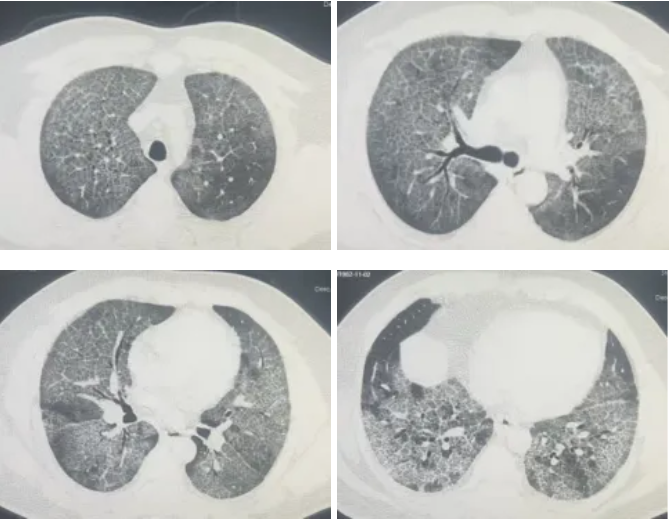

接诊后,呼吸与危重症医学科冯永海团队对孟师傅的胸部CT进行了细致分析,发现双肺弥漫性改变,高度怀疑肺泡蛋白沉积症。

▲ 灌洗前胸部CT